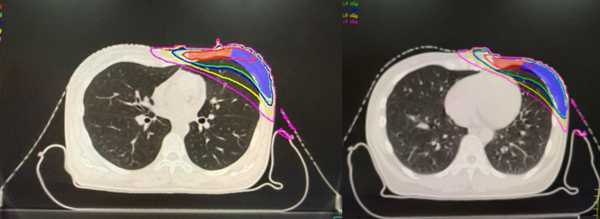

徐利明主任在电脑上打开一幅人体解剖图,细致地讲解起来:“深吸气屏气技术,英文简称DIBH,是通过让患者在深吸一口气后屏住呼吸,再进行放疗。当你深吸气时,膈肌会下降,肺部充分扩张,这样就会把心脏向下、向后‘推挤’移位,让它远离左侧胸壁需要照射的区域,从而显著降低心脏受到的辐射剂量。”

(图:自由呼吸与DIBH下心脏位置对比示意图)

定位完成后,物理师团队开始在李女士的“深吸气屏气”影像上设计放疗计划。他们精心优化剂量分布,确保肿瘤靶区获得足够剂量的同时,将心脏的平均受照剂量控制在5Gy以下,肺部受量也同步降低。经过反复计算与模拟,一个安全、可行的治疗方案终于确定。

(图:剂量分布优化示意图)